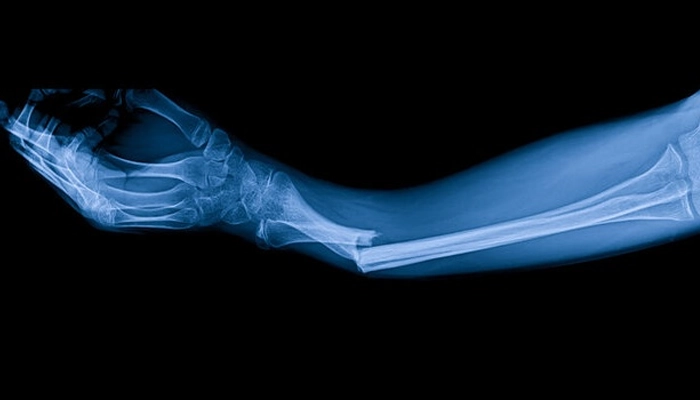

Bác sĩ sẽ dựa vào phim chụp X-quang hoặc CT Scan để quyết định:

Dựa vào việc hết đau khi tì đè, khả năng vận động bình thường và quan trọng nhất là hình ảnh can xương lấp đầy ổ gãy trên phim chụp X-quang.